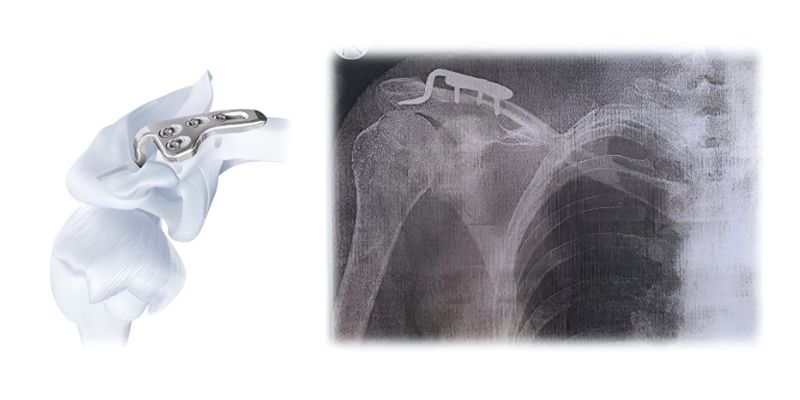

A) Σταθεροποίηση με Πλάκα (Hook Plate)

- Γίνεται μικρή τομή και τοποθετείται ειδική πλάκα που ανατάσσει την άρθρωση και σταθεροποιεί την κλείδα.

- Οι ραγέντες σύνδεσμοι συρράπτονται.

- Η πλάκα αφαιρείται μετά από 4–5 μήνες.

- Κατά την περίοδο αποκατάστασης αποφεύγεται η άρση του άνω άκρου άνω των 90°.

- Πλεονέκτημα: υψηλή σταθερότητα.